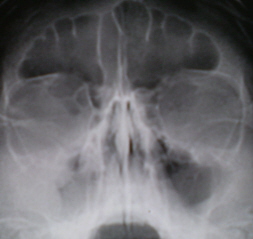

Бытующее в литературе утверждение, что «чаще всего кисты исходят из нижних стенок пазух» также довольно спорно. Ниже мы приводим несколько иллюстраций из практики. Иллюстрации 13, 14, 15, 16, 17.

Иллюстрация 13. Справа пристеночно у латеральной, и частично у верхней стенок гайморовой полости, дифференцируются два полукруглых затемнения средней интенсивности, однородной структуры, с чёткими, ровными контурами. Слева определяется общая неоднородность тени левой гайморовой полости, пристеночно определяется снижение прозрачности, по всей видимости, за счет разрастания фиброзной ткани. Определяется также неоднородность тени лобной пазухи.